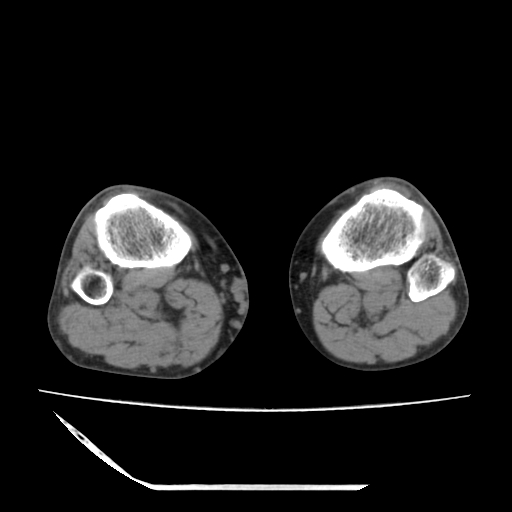

标题: CT13225:老年男性,左膝关节疼痛数月;请各位老师讨论。 [打印本页]

标题: CT13225:老年男性,左膝关节疼痛数月;请各位老师讨论。

骨质增生,骨性关节面硬化,关节积液,考虑退行性骨关节病

关节腔内少量积液,关节面退变。

双膝退变

骨质增生,骨性关节面硬化,关节间隙失常,关节积液,考虑退行性骨关节病.

骨质增生,骨性关节面硬化,关节积液,考虑退行性骨关节病。

这个病例诊断:退行性骨关节炎